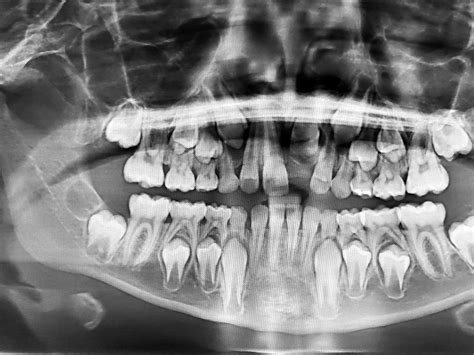

Exploración Radiográfica

La radiografía panorámica del 21 de noviembre de 2004 aportada por la paciente mostraba una pérdida ósea horizontal generalizada en el tercio coronario de la raíz (localizado hasta el tercio medio radicular). En los dientes 17, 16, 15, 47 y 48 se apreciaban áreas radioopacas debidas a la presencia de cálculo. En los dientes 37, 35, 44, 45, 46 y 47 se constató un ensanchamiento del espacio periodontal. Así mismo, se observó una imagen radiolúcida en la zona interradicular del diente 46 provocada por una osteólisis.